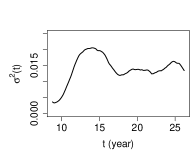

The estimated variance of the measurement error is by the method proposed in Section 3, by PACE and by LM, respectively. The estimates of the covariance surface are depicted in Figure 3. We observe that, the estimates produced by SNPTM and SNPTF are similar in the diagonal region, while visibly differ in the off-diagonal region. For this dataset, the upward off-diagonal parts of the estimated covariance surface by SNPTF seem artificial, so we recommend the SNPTM estimate for this data. For the PACE estimate, due to the missing data in the off-diagonal region and insufficient observations at two ends of the diagonal region, it suffers from significant boundary effect.

The mean function estimated by SNPTM111SNPTM, SNPTF and PACE use the same method to estimate the mean function. shown in the left panel of Figure 4 and found similar to its counterpart in Lin et al. (2019), suggests that the spinal bone mineral density increases rapidly from age 9 to age 16, and then slows down afterward. The mineral density has the largest variation around age 14, indicated by the variance function estimated by SNPTM222SNPTM and SNPTF use the same method to estimate the variance function. and shown in the middle panel of Figure 4. As a comparison, the PACE estimate, shown in the right panel of Figure 4, suffers from the boundary effect that is passed from the PACE estimate of the covariance function, because the PACE method estimates the variance function by the diagonal of the estimated covariance function.